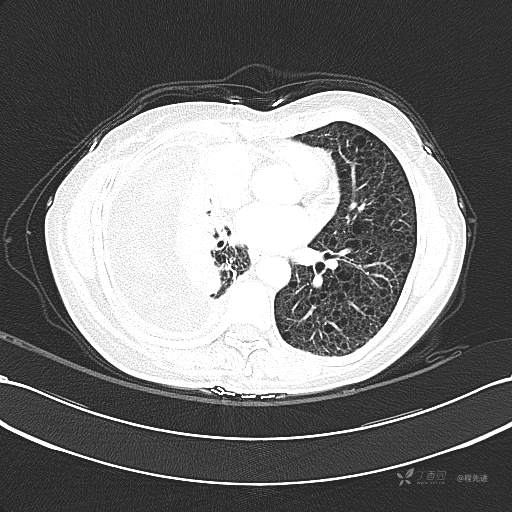

患者性别:女

患者年龄:51岁

简要病史:胸闷半年